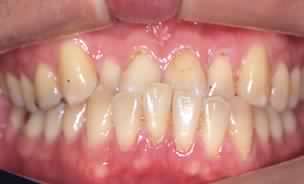

Le manifestazioni cliniche ed i disturbi che vengono conseguenti la malocclusione, sono fenomeni a cascata che possono essere osservati e documentati:

• Abrasioni degli elementi dentari sottoposti a trauma

• Recessioni gengivali

• Recessioni parodontali, fino alla Malattia Parodontale o piorrea